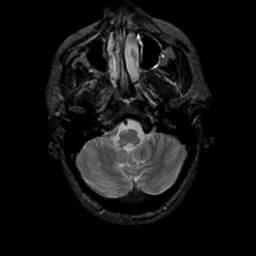

MR Study #19, August 25, 1991 -- Slice #8

[Home][Help][Clinical][Tour 1][Tour 2] Slice 8